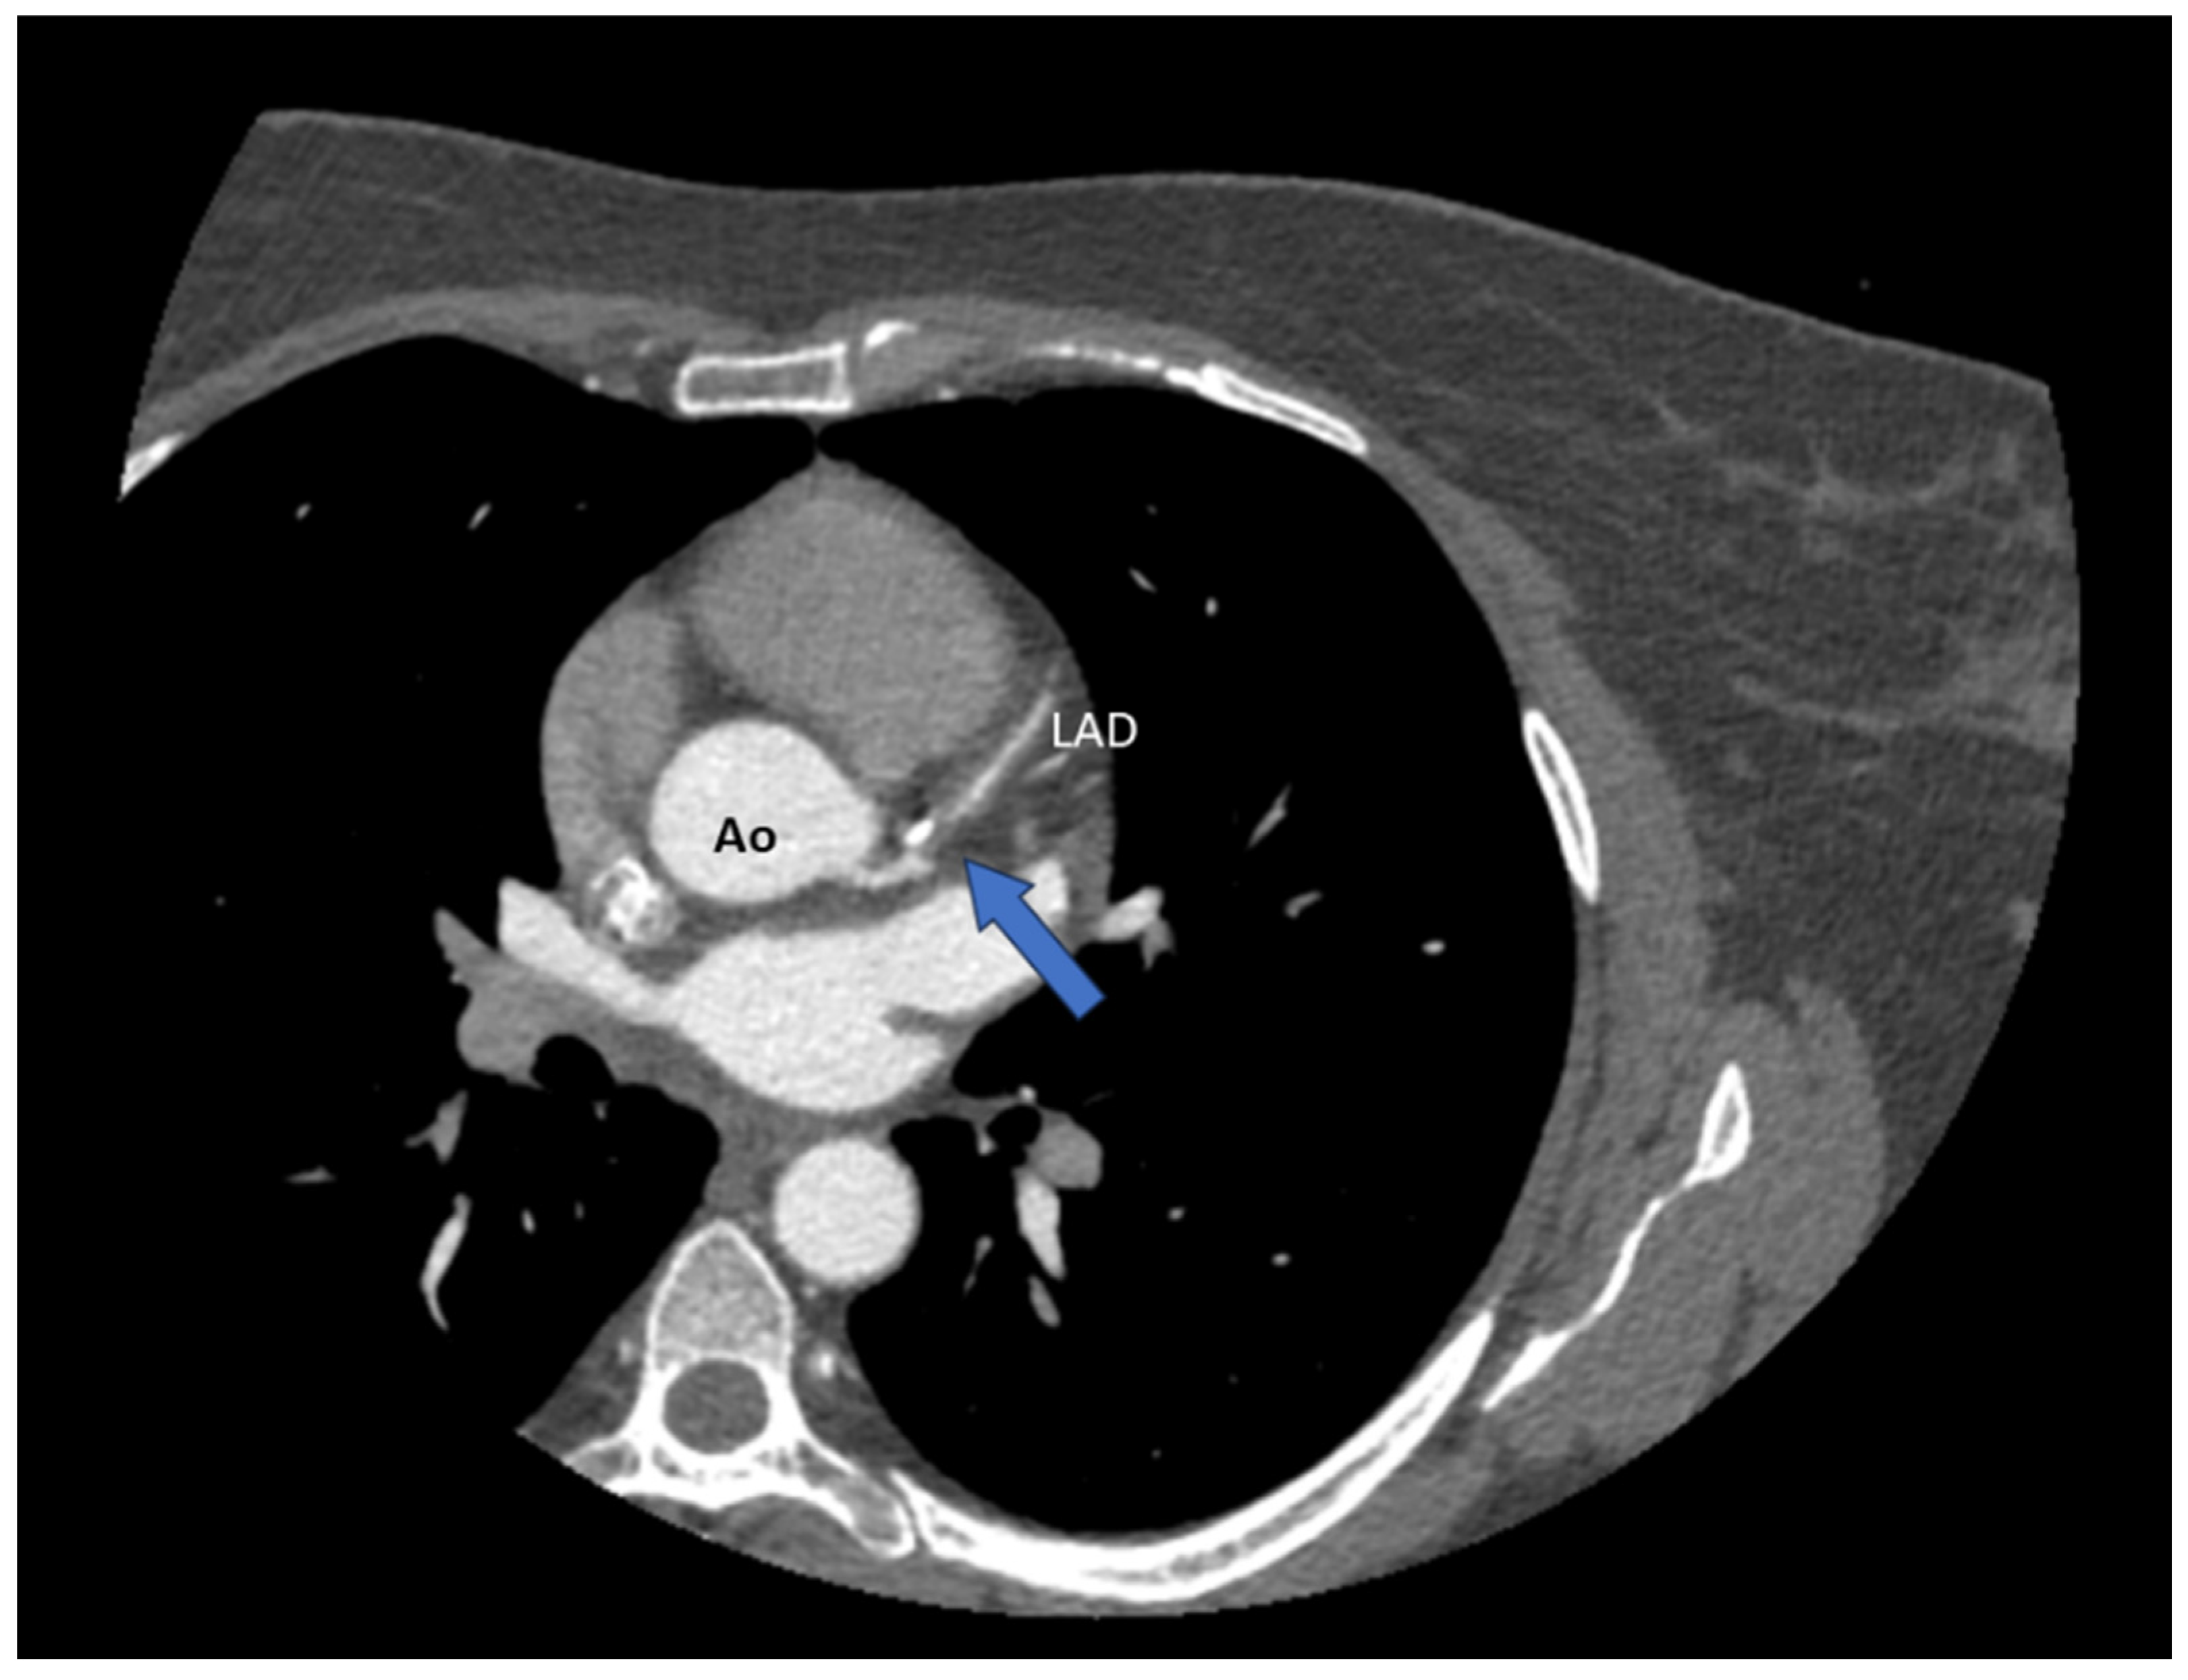

Spontaneous Coronary Artery Dissection Involving the Left Main with Extension to Left Anterior Descending Artery and Left Circumflex Artery: Diagnostic and Management Challenges

Rusali, C.A.; Cojocaru, L.; Lupu, I.C.; Uzea, C.-D.; Rusali, M.L. Spontaneous Coronary Artery Dissection Involving the Left Main with Extension to Left Anterior Descending Artery and Left Circumflex Artery: Diagnostic and Management Challenges. Diagnostics 2025, 15, 61. https://doi.org/10.3390/diagnostics15010061